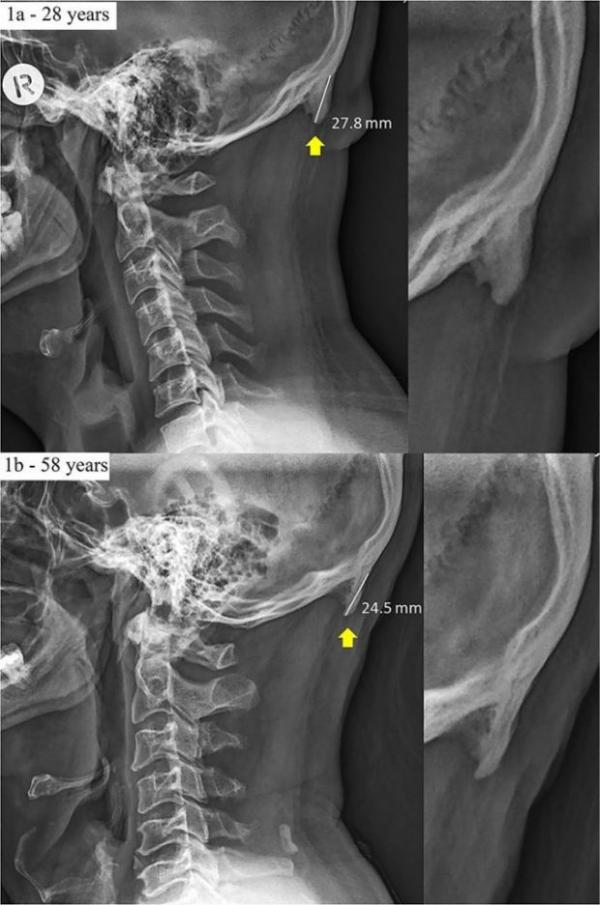

تصویری از استخوان اضافی در گردن افراد مورد آزمایش

طبق مطالعات دانشمندان دانشگاه سان شاین کوست استرالیا، به طور متوسط طول استخوان اضافی در گردن افراد مورد آزمایش ۱ اینچی (۲.۵ سانتیمتر) بوده است. در برخی موارد، طول آن به ۱.۵ اینچ نیز رسیده بود. تا حدود یک دهه پیش، هرگز چنین چیزی در بدن افراد جوان رویت نمیشد. به همین دلیل اکنون صحبت آغاز تکاملی دیگر در ساختمان اسکلت بدن انسان مطرح شده است